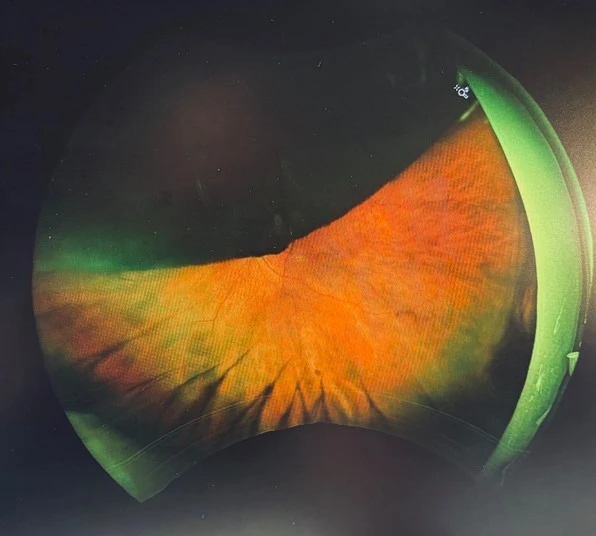

On further examination the patient was found to have a large pigmented choroidal mass taking up most of the superior fundus. B-Scan ultrasound displayed a large choroidal mass with low internal reflectivity a finding highly correlated with choroidal melanoma. Prognosis depends on tumour size, cytogenetic profile, and presence of metastases, with the liver being the most common site of distant spread.

Large superior pigmented choroidal mass